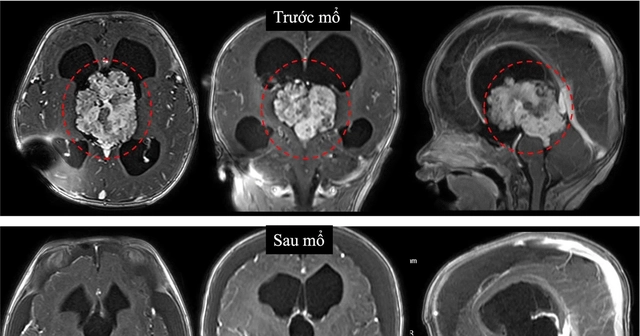

Vị trí khối u trong não của bệnh nhi trước và sau phẫu thuật

Qua thăm khám, bác sĩ ghi nhận vòng đầu của bé lớn hơn bình thường, thóp căng phồng. Siêu âm qua thóp phát hiện có khối u nằm trong não, gây chèn ép làm não bị giãn. Đây là tình trạng bệnh thường gọi là não úng thủy. Kết quả chụp cộng hưởng từ sau đó xác định khối u nằm ở não thất III, một “khoang” nằm sâu gần trung tâm não, nơi chứa dịch não tủy.

Theo phân tích của BS Huy, vị trí này đặc biệt nguy hiểm vì xung quanh là nhiều cấu trúc thần kinh và mạch máu quan trọng. Việc can thiệp phẫu thuật vì thế luôn tiềm ẩn rủi ro cao, nhất là với bệnh nhi còn quá nhỏ. Kết quả xét nghiệm mô bệnh học cho thấy đây là u đám rối mạch mạc không điển hình độ 2, một dạng u hiếm gặp của hệ thần kinh trung ương.

Trước nguy cơ phẫu thuật sớm có thể gây biến chứng, các bác sĩ và gia đình đã thống nhất đặt ống dẫn lưu từ não xuống ổ bụng để giảm áp lực tạm thời, giúp bé ổn định và chờ thời điểm phù hợp hơn để mổ. Tuy nhiên, chỉ sau 3 tháng, khối u phát triển nhanh, kích thước tăng gấp nhiều lần. Trước diễn tiến nguy hiểm này, các bác sĩ buộc phải quyết định phẫu thuật sớm để cứu bệnh nhi.